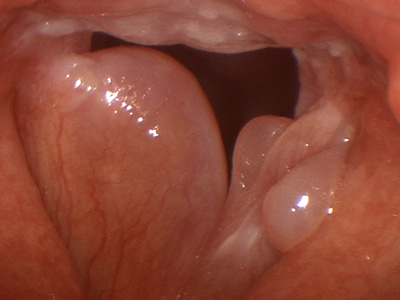

ΠΟΛΥΠΟΔΕΣ ΦΩΝΗΤΙΚΩΝ ΧΟΡΔΩΝ

Οι πολύποδες είναι συνήθως μονήρεις μισχωτές ή με εύρεια βάση μάζες στις

γνήσιες φωνητικές χορδές και εμφανίζονται πιο συχνά στους άνδρες.

Βασικό σύμπτωμα : βράγχος φωνής και φωνητική κόπωση.